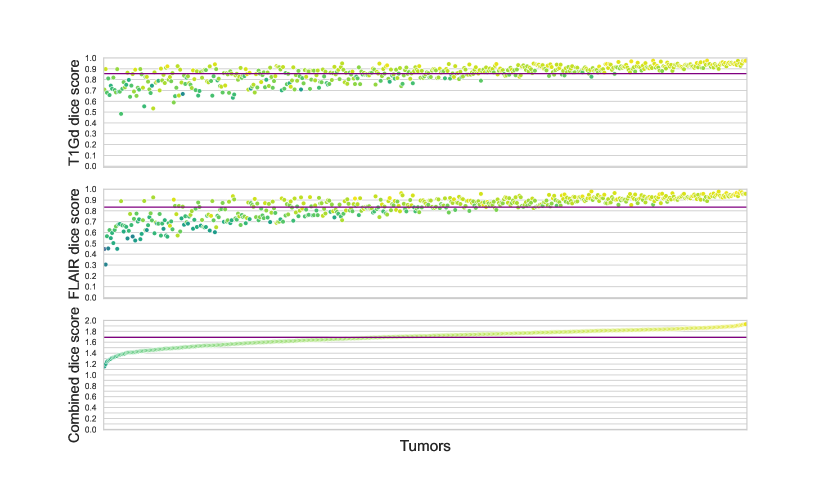

Tab.2 showcases how the difference between real and synthetic data distributions affects the query accuracy. Given there is an evident gap between real tumor progression and the tumor growth trajectory modeled by the reaction-diffusion model, we expectedly observe ca. 10 percent drop of the accuracy. Fig. 2 and 3 demonstrate the same difference in real and synthetic data distributions for every example used in the study. In a way, in future works probing more complicated tumor descriptions, such analysis can serve as a measure of plausibility of a tumor growth model.